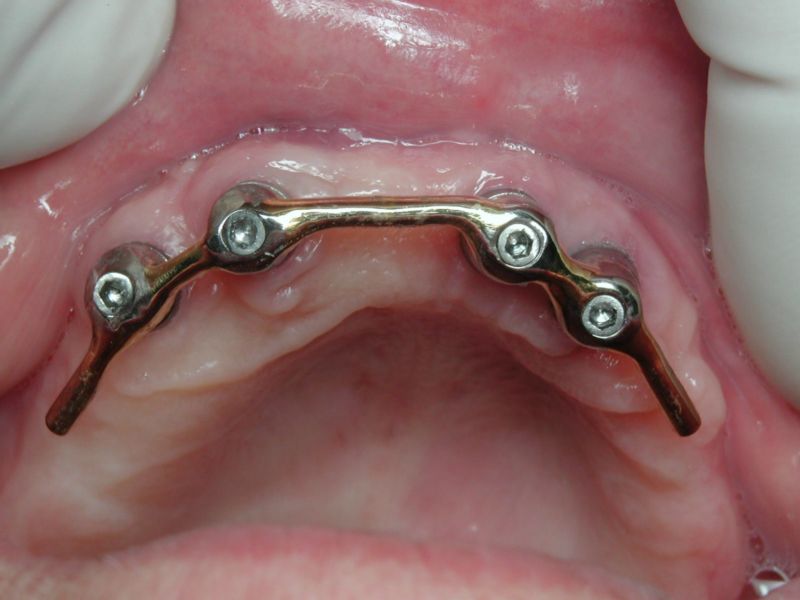

- Barre de Dolder à la mandibule

Résorption postérieure importante et compression du canal dentaire

La prothèse sur boutons-pression n’est soutenue efficacement que dans la zone antérieure

Dans le cas de résorption importante, une compression du canal dentaire est possible postérieurement

Il est préférable de choisir une option de barre avec des cavaliers distaux afin de diminuer cette compression postérieure :

Tout en sachant que la pression verticale sur ces cavaliers distaux entraînera plus de maintenance (perte possible d’un cavalier ou fracture etc…) par rapport à une barre avec un seul cavalier central qui aura une possibilité de légère rotation sur la barre en cas de pressions importantes appliquées sur les zones molaires.